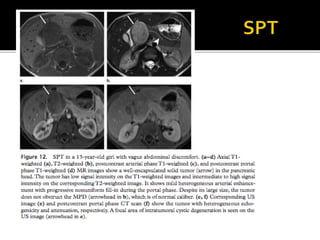

 Características

morfológicas:

 Grande x: 9 cm.

 Crecimiento lento.

 Masa bien encapsulada.

 Cola > cabeza.

 Desplaza más que invade,

raro obstrucción biliar

 Hipodenso enTC, baja

señal enT1 yT2.

 Hemorragia interna y

degeneración quística

 Hemorragia hiper-aguda:

hiperintensa enT1 con intensidad

de señal variable enT2.

 Hemorragia crónica: hipointensa

en ambas secuencias.

 Nivel fluido-fluido/ fluido –debris:

10-18% por efecto del

hematocrito.

 Calcificaciones periféricas 30%.

 Realce heterogéneo periférico

durante la fase arterial y realce no

uniforme periférico pero

agresivo. (realce menor que el

páncreas)